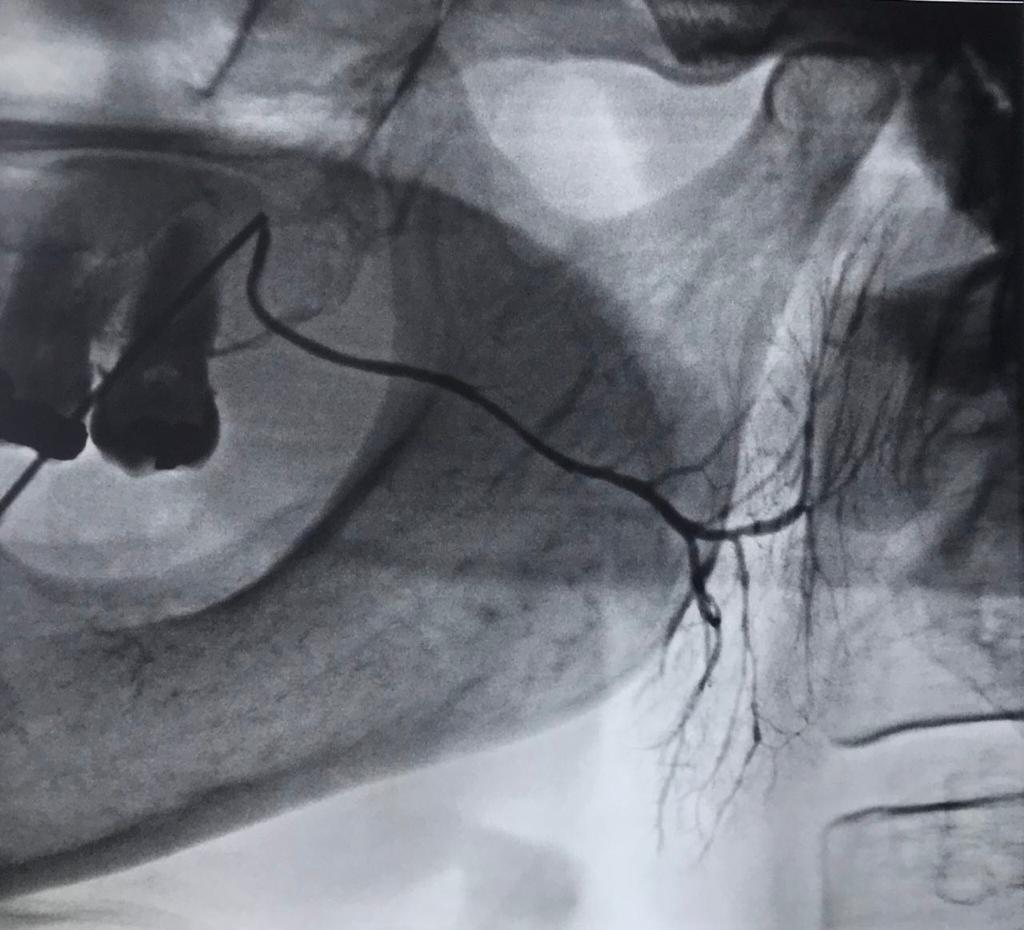

Sialography is one of the radiographs related to salivary glands and in addition to evaluating the gland parenchyma, it is the best method for evaluating salivary gland ducts.

In sialography, contrast material is injected in the salivary gland duct in reverse and at different stages radiographs are prepared with special techniques to examine the salivary glands and the presence or absence of salivary gland stones.